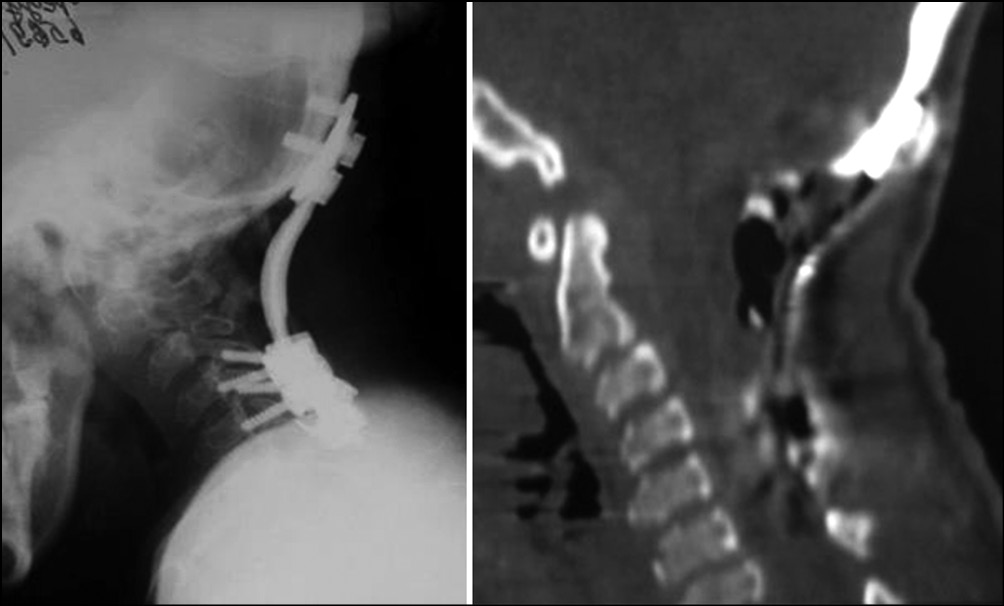

Пациентка обратилась в НМИЦ ТО им. Н.Н. Приорова с клиникой тетрапареза. Учитывая прогрессирующую неврологическую симптоматику, рекомендовано хирургическое лечение в срочном порядке. В отделении патологии позвоночника выполнена операция: наложение гало-кольца. Ламинэктомия позвонков С1, С2, С3, резекция заднего края большого затылочного отверстия, декомпрессия спинного мозга, окципитоспондилодез С0–С6, задний спондилодез аутокостью (рис. 3). На момент выполнения операции пациентке было 15 лет. Через 2 нед. после проведенного лечения в неврологическом статусе отмечается положительная динамика (ASIA B>>C). При контрольном осмотре через 6 мес. — ходит с поддержкой. Через 1 год после операции — передвигается самостоятельно.

Рис. 3. Рентгенограмма и компьютерная томограмма шейного отдела позвоночника после операции, положение металлоконструкции правильное